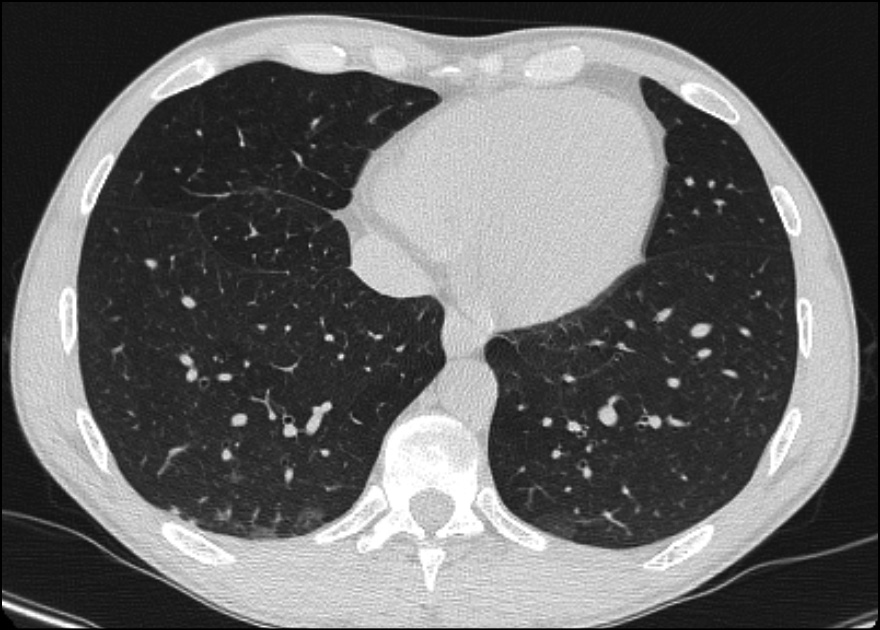

We performed a wide range of microbiological tests and all turned out negative: a respiratory panel film array on nasal swab (for viruses and bacteria causing common pneumonia), urinary Legionella and Pneumococcus Antigens, Interferon Gamma Release Assay (IGRA) test, serum beta-D-glucan and galactomannan, Widal-Wright reaction, IgM/IgG Rickettsia . Given these data, we excluded most of the common causes of pneumonia. HIV viral load on day 2 was not detected, CD4+ count was >600 cells/µL (31%) with a CD4+/CD8+ ratio 0.7. Serology for syphilis turned out positive: RPR 1:32 and TPPA 1:40,960. After a brief literature research, we noticed that in some cases, syphilitic pneumonia may present with nodular lesions. So we decided to search Treponema pallidum DNA on bronchoalveolar lavage (BAL) in addition to more common pneumonia pathogens. On day 6 the following microbiological tests on bronchoalveolar lavage (BAL) were performed: culture for bacteria/fungi, PCR and Ziehl-Neelsen for mycobacteria, galactomannan, Aspergillus DNA, Pneumocystis jirovecii DNA, film array panel for virus/bacteria. All these results were negative, except for Treponema pallidum DNA, that turned out positive. So, antibiotic therapy was switched on intramuscular Benzylpenicillin 2.4 MU daily. However, after 4 days of ceftriaxone therapy, we had noticed an improvement in blood test with reduction in inflammatory markers (CRP 3 mg/dL, AST 44 U/L, ALT 64 U/L, total bilirubin 1.46 mg/dL) and an improvement in respiratory performance (on day 6, the patient’s saturation was 98% in VM 24%). This could be related to the fact that ceftriaxone is also a second line therapy for syphilis. On day 10 the patient was discharged with a normal oxygen saturation level in room air, CRP 2.1 mg/dL, AST 53 U/L, ALT 82 U/L, alkaline phosphatase 792 U/L, GGT 300, bilirubin 1.03 mg/dL. Due to mild elevation in liver enzymes seven days course of doxycycline 100mg bid was prescribed. Three months after discharge, the patient performed a follow-up blood test examination that was unremarkable, as well as HIV-RNA and CD4+ count, and serology for syphilis that showed a negative RPR and a reduced TPPA 1:5,120 and a pulmonary CT scan that showed a volumetric reduction of the nodular lesions on both lungs (Figure 2).

Figure 2 - Pulmonary CT scan performed 3 months after discharge showed a volumetric reduction of the nodular lesions on both lungs.